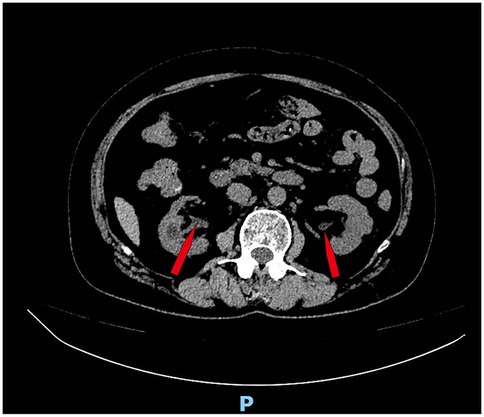

Six months after the operation, the patient returned to the hospital for follow-up review, the creatinine level decreased to normal, the bladder volume expanded to 400 ml, and acute pyelonephritis did not occur. Because of concerns about the risk of urinary tract infection, cystography was not performed to determine whether the vesicoureteral reflux was improved. We ordered a CT scan of the patient, which showed no dilated ureter (Figure 3).

Figure 3. CT scan showed no dilated ureter (Figure 3, red arrow).